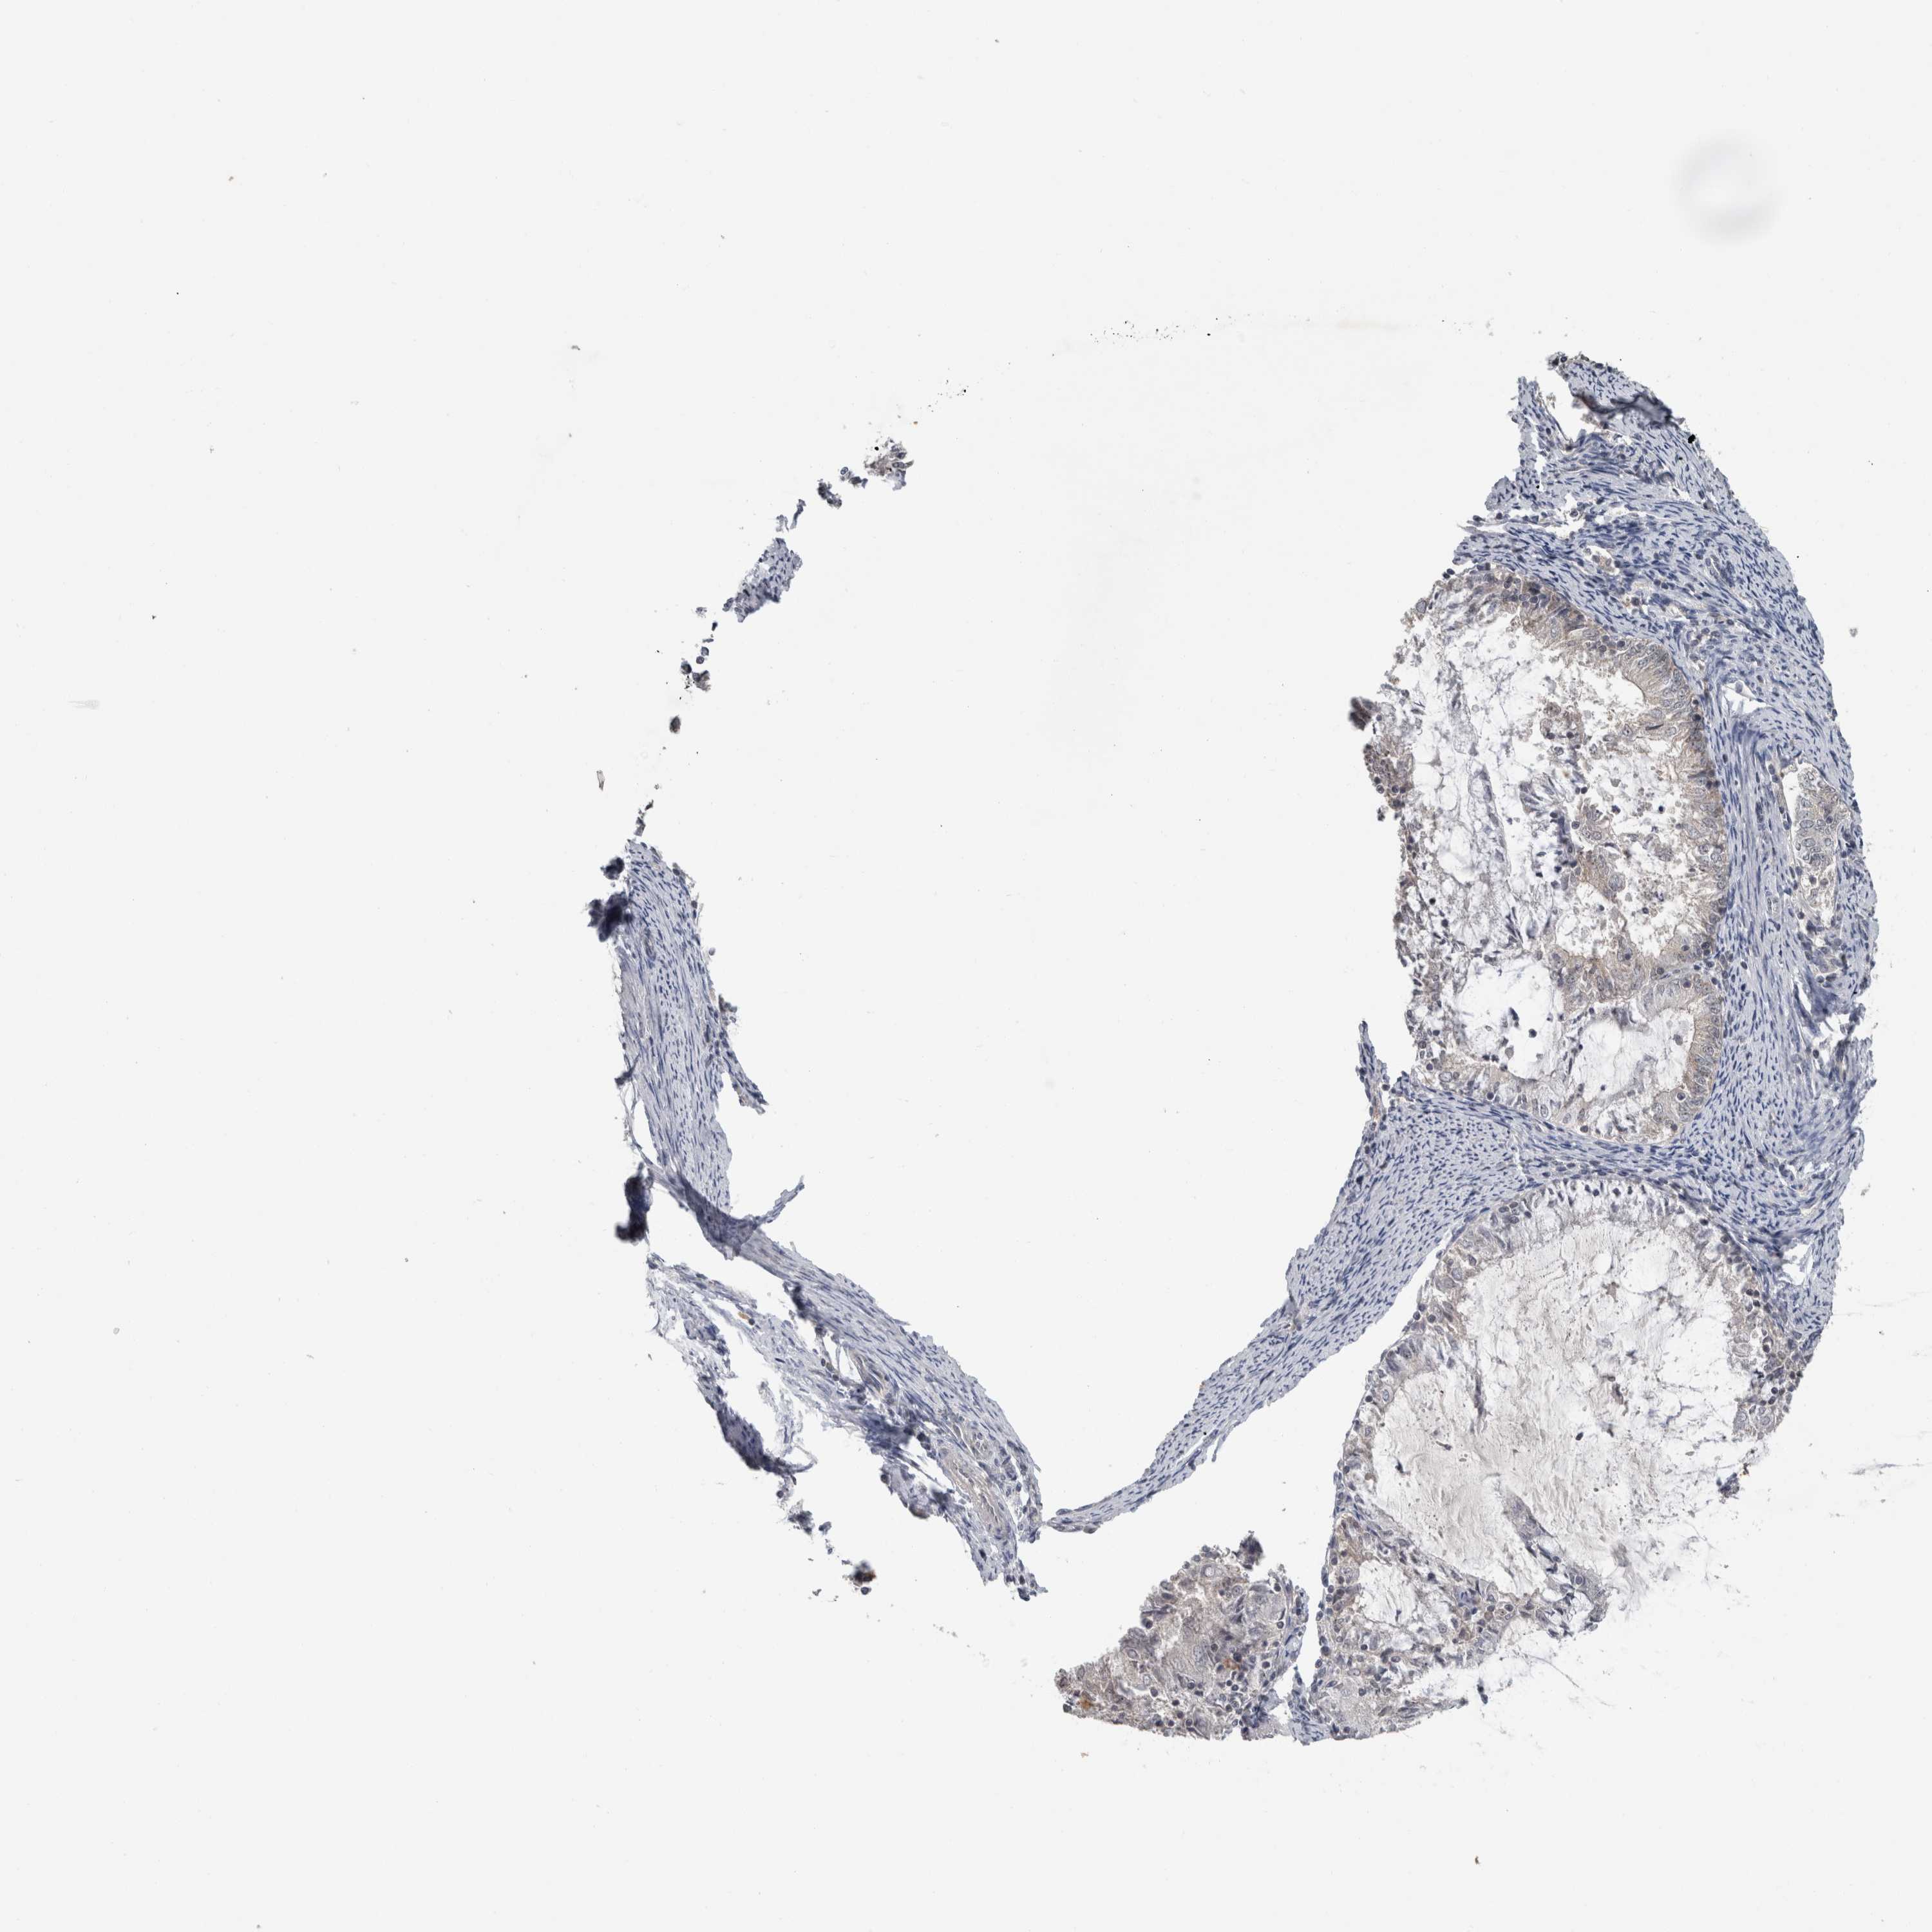

ENDOMETRIAL CANCER - Protein expressioni

A mouse-over function shows sample information and annotation data. Click on an image to view it in a full screen mode. Samples can be filtered based on level of antibody staining by selecting one or several of the following categories: high, medium, low and not detected. The assay and annotation is described here.

Note that samples used for immunohistochemistry by the Human Protein Atlas do not correspond to samples in the TCGA dataset.

Antibody stainingi

Antibody staining in the annotated cell types in the current human tissue is reported as not detected, low, medium, or high, based on conventional immunohistochemistry profiling in selected tissues. This score is based on the combination of the staining intensity and fraction of stained cells.

Each image is clickable and will lead to virtual microscopy that enables deeper exploration of all samples and also displays staining intensity scores, fraction scores and subcellular localization as well as patient and tissue information for each sample.

Antibody HPA019058

Antibody HPA026672

Staining

High

Medium

Low

Not detected

Intensity

Strong

Moderate

Weak

Negative

Quantity

>75%

75%-25%

<25%

None

Location

Nuclear

Cytoplasmic/membranous

Cytoplasmic/membranous,nuclear

Adenocarcinoma, metastatic, NOS